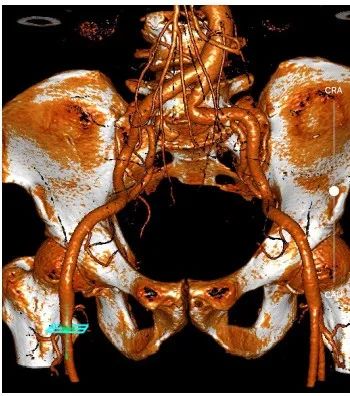

为确保手术过程万无一失,手术后患者能尽快恢复,团队全体成员反复沟通、讨论,应用医用软件分析出多方位参数,并制定各种风险的应急处理方案。

7 月 20 日,在院领导、医务部和供应链部等支持下,合肥京东方医院心血管学部联合麻醉科、手术部、超声科、重症医学科等多学科团队成功开展该例经导管主动脉瓣置换术(TAVR 手术)。

全麻后,成功穿刺右股动脉,通过穿刺点输送系统将瓣膜输送至病变的主动脉瓣处,经过严密地心电监护、心脏食道超声引导,手术团队在心室快速起搏下,使得收缩压降到 60 mmHg、脉压差小于 10 mmHg,此时释放人工生物瓣膜取代自身病变的瓣膜,食道超声检查无瓣周漏,人工瓣膜工作正常,手术完美结束。